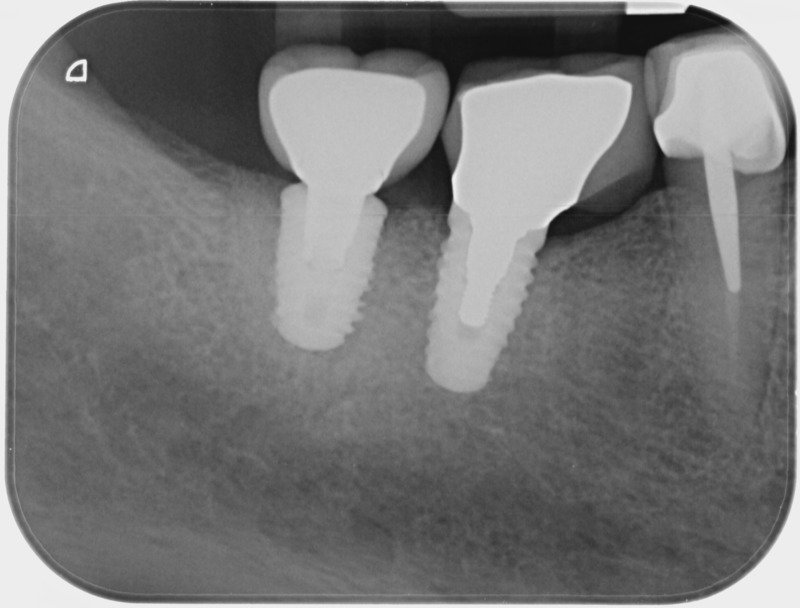

• Couronnes sur implants : Lorsqu’un implant est posé en remplacement des racines d’une dent, il est conçu pour recevoir d’abord un pilier vissé puis une couronne céramique. Le couple couronne - implant se substitue à la dent manquante pour en assurer les mêmes fonctions. Nous pouvons également adapter un bridge sur plusieurs implants dans le cas d’un édentement plus important.

Après